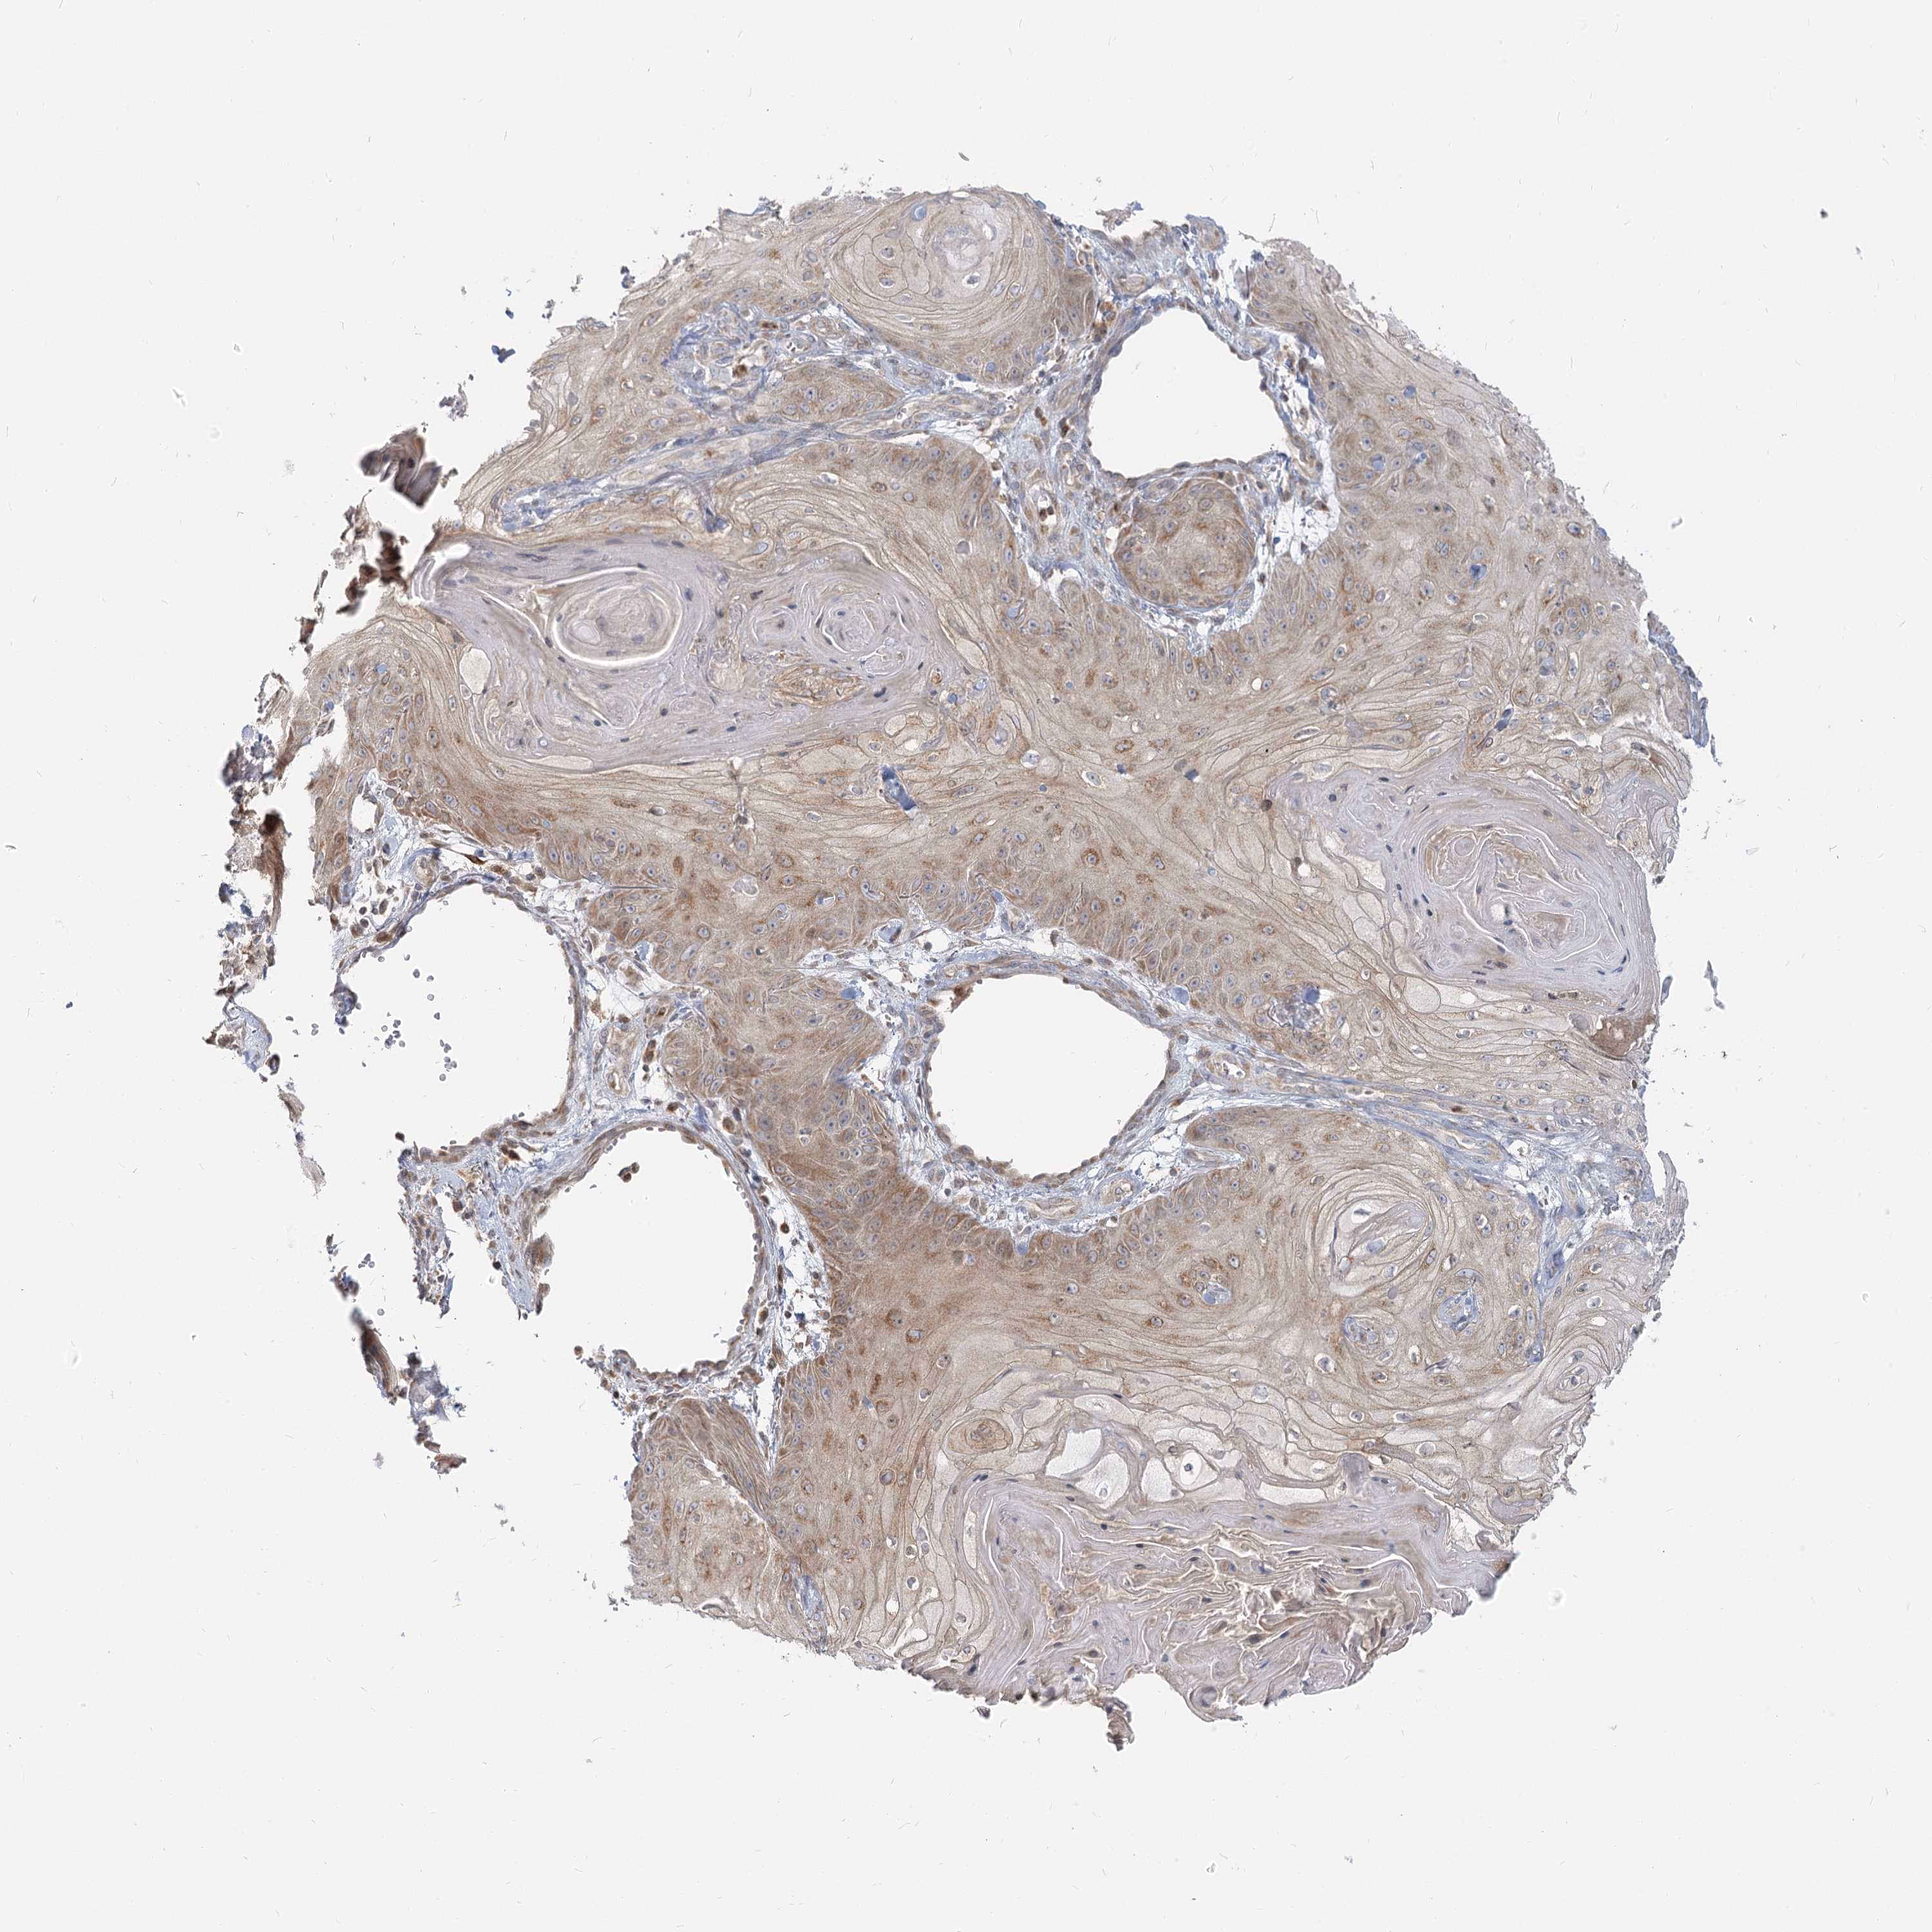

Basal cell and squamous cell cancer

SKIN CANCER - Protein expressioni

A mouse-over function shows sample information and annotation data. Click on an image to view it in a full screen mode. Samples can be filtered based on level of antibody staining by selecting one or several of the following categories: high, medium, low and not detected. The assay and annotation is described here.

Each image is clickable and will lead to virtual microscopy that enables deeper exploration of all samples and also displays staining intensity scores, fraction scores and subcellular localization as well as patient and tissue information for each sample.

Antibody HPA034515

Basal cell carcinoma